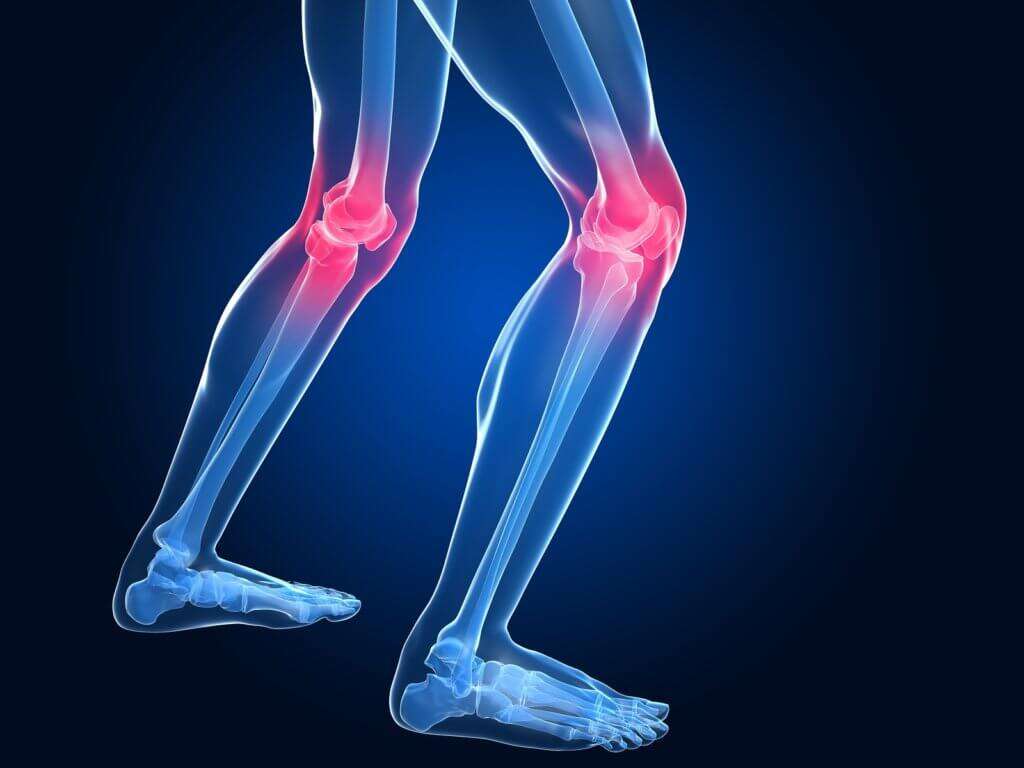

Knee Osteoarthritis

Total Knee Replacement